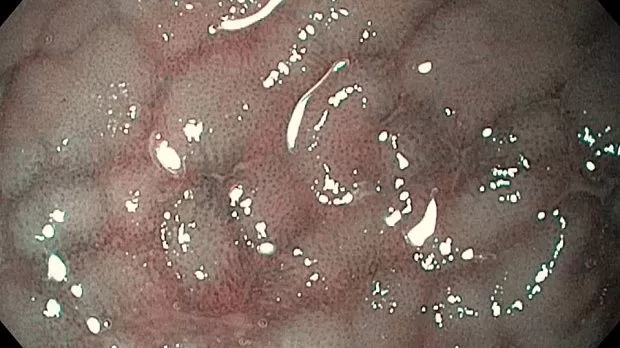

Публикации из социальных сетей: “Cobblestone esophagitis” (эзофагит со слизистой булыжной мостовой)

“Cobblestone esophagitis” (эзофагит со слизистой булыжной мостовой) - редкая эндоскопическая находка и ассоциируется с эозинофильным эзофагитом, кандидозом и пищеводом Барретта у взрослых. Он также может быть найден при тяжелом рефлюкс-эзофагите, вторичен к дистальной обструкции гастроинтестинального тракта. В нашем случае - это пациент после с 9-летним стажем бандажирования кардиального отдела желудка, признаками дуоденостаза, фундальной эрозивной гастропатией, расширением пищевода и уровнем жидкости в нем при горизонтальном положении, грыжи ПОД, эрозивно-язвенном дистальном эзофагите.. Пациент просто пришел удалить полип в прямой кишке и заодно посмотреть, что творится в желудке.... Ацетообеление+NBI+биопсия. ИПП на 3-4 мес и повтор для решения о Барретте.